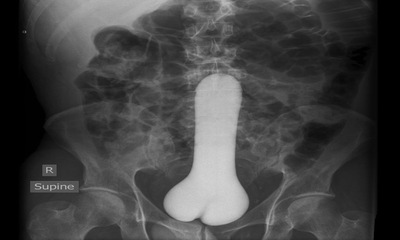

DTC : si ça passe difficilement, ça ne ressortira pas facilement !

Petite leçon d'anatomie aujourd'hui. Dans le cadre d'une pénétration anale, tout corps étranger qui a passé le sphincter interne (muscle circulaire situé juste après l'entrée de l'anus et sur lequel nous n'avons aucun co...